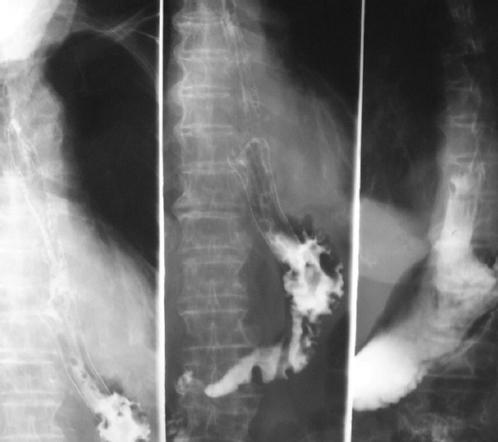

A chest tube was inserted under local anesthesia to drain the hydropneumothorax and the patient was submitted to a computed tomography (CT) scan of the chest and abdomen which also demonstrated the same findings of pneumomediastinum and hydropneumothorax and subcutaneous emphysema of the left hemithorax with no significant findings from the abdominal cavity (Fig. 1). A possible diagnosis of spontaneous esophageal rupture was considered which was confirmed with a gastrografin esophagography demonstrating a rupture in the left lower third of the esophagus (Fig. 2).

Figure 2 Thoracoabdominal computed tomography scan showing pneumothorax. A: pneumomediastinum and subcutaneous emphysema. B: hydropneumothorax, pneumomediastinum and subcutaneous emphysema. C: no significant findings from the abdomen except subcutaneous emphysema.